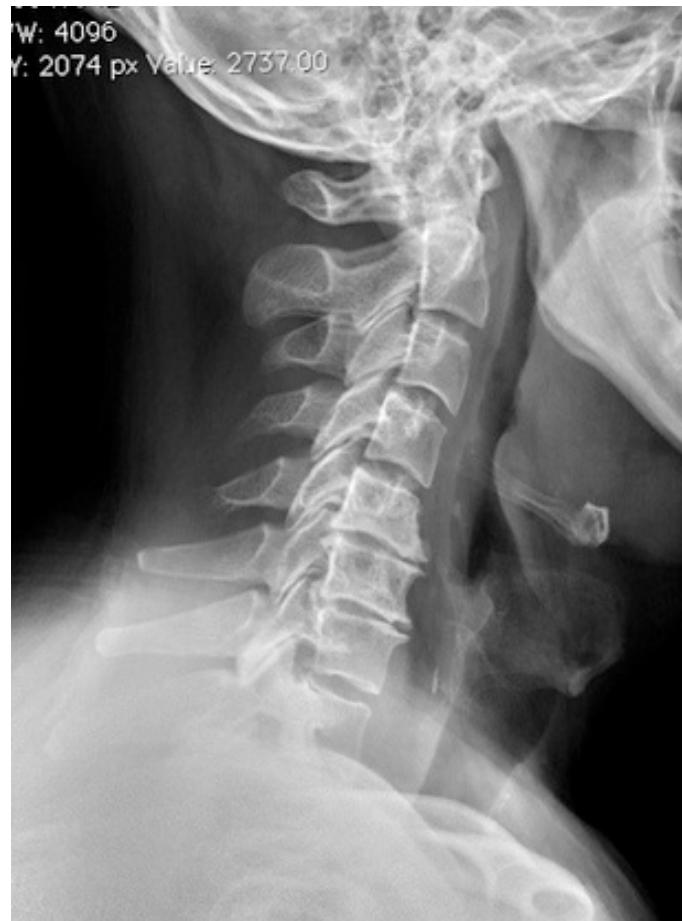

Cervical Spondylosis

- Pathophysiology: Natural aging and degenerative process of cervical motion segment

- Age of onset: Typically begins at age 40-50; 85% of patients >65 years

- Presentation: Can lead to cervical radiculopathy, cervical myelopathy, or axial neck pain

- Diagnosis: Plain radiographs of cervical spine

- Treatment: Observation, medical management, or surgical management depending on severity and chronicity of pain, presence of instability, or neurological deficits

Imaging Examples:

Surgical Treatment - Anterior Cervical Discectomy and Fusion: